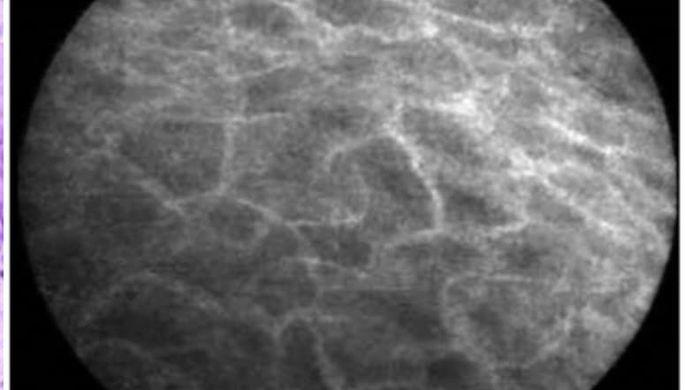

Для создания карты исследователи проанализировали более 20 000 изображений клеточных структур, полученных с помощью флуоресцентной микроскопии. Благодаря этому подходу удалось выделить 275 отдельных белковых комплексов, а также определить 975 ранее неописанных функций белков. Например, недавно открытый белок C18orf21 теперь связывают с участием в обработке РНК, а DPP9, известный своей способностью расщеплять белки, показал связь с интерфероновой сигнализацией, важной для борьбы с инфекциями.